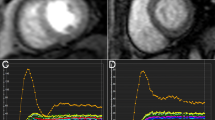

LV global native T1 and ECV values were significantly higher in T2DM patients than in controls (native T1: 1035.02 ms ± 26.65 ms vs. 1060.17 ms ± 43.63 ms, p = 0.005; ECV: 26.33% ± 2.81% vs. 30.75% ± 3.65%, p < 0.001). In addition, ECV values in the G1, G2, and HT patients (29.59% ± 3.90%, 31.92% ± 3.05%, and 29.22% ± 6.58%, respectively) were significantly higher than those of controls (all p < 0.05). G2 patients had statistically significantly higher ECV values than both the G1 (p = 0.032) and the HT patients (p = 0.042) (Fig. 2). Nevertheless, there was no statistical difference for post contrast T1values across the G1 and G2 patients (see Table 2).

Histogram of ECV and GLS mean values for each group. A showed that ECV in the diabetic group, G1, G2 and HT groups was significantly higher than that in Cs, and ECV in G2 was significantly higher than that in G1 and HT group. B showed that GLS in the diabetic group, G1, G2 and HT groups was significantly lower than that in Cs, and GLS in G2 was significantly lower than that in G1 and HT group

GLS was significantly decreased among T2DM patients as compared with controls (–16.51% ± 2.53% vs. –19.66% ± 3.21%, p < 0.001). LV myocardial deformation assessment revealed no significant difference in GCS and GRS values between T2DM patients and controls.

A comparison across the G1, G2, and HT patients showed that GLS was significantly decreased in the G2 patients (–15.75% ± 2.29%) as compared with the G1 (–17.27% ± 2.57%) and the HT patients (–17.54% ± 3.09%) (all p < 0.05; see Fig. 2). No significant difference was observed in either GRS or GCS values across the three groups (see Table 2).